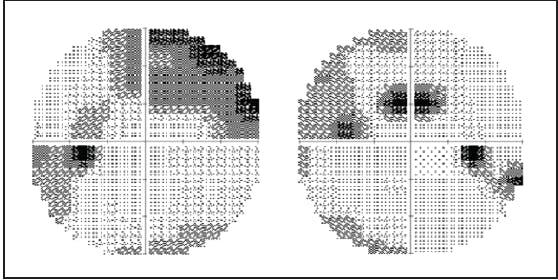

On examination, UCVA is 20/30 OU, and IOP is 14 mm Hg OU. A slit-lamp examination reveals a scarred trabeculectomy in the right eye, a well-positioned IOL in each eye, and no active hyphema. On gonioscopy, the appearance of the stent in the nasal angle of each eye is unremarkable (Figure 1). A fundus examination reveals cupping of both optic nerves. Visual field testing demonstrates stable superior arcuate scotomas in both eyes, and OCT shows cupping and thinning of the retinal nerve fiber layer in both eyes (Figures 2 and 3).

Figure 3. OCT shows cupping of the optic nerve and thinning of the retinal nerve fiber layer in each eye.